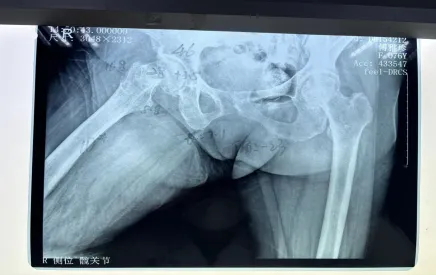

但不幸再次降臨,阿婆在家起床時不慎摔倒,右髖部疼痛難忍,經(jīng)過醫(yī)院檢查后確認,傅阿婆為右側(cè)股骨頸骨折。

阿婆住院后,羅院長立馬聯(lián)系內(nèi)科和麻醉科專家來會診,積極調(diào)整阿婆各項不理想指標(biāo),盡量將手術(shù)風(fēng)險降到最低。羅院長還針對阿婆病情特殊情況進行一對一的計算機三維精準(zhǔn)規(guī)劃,精心打造出詳細的手術(shù)方案,經(jīng)過羅院長手術(shù)團隊的努力,阿婆成功完成了機器人輔助下右側(cè)人工雙動股骨頭置換術(shù)。